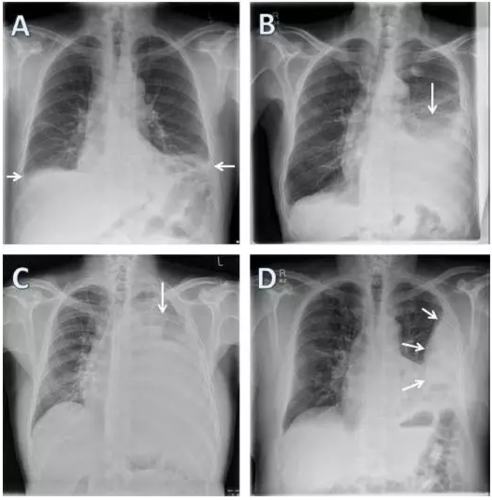

胸腔积液的x线表现

胸腔积液的x线表现,气胸的x线表现

基础 x线表现胸腔积液 少量积液 中量积液 大量积液 10

经典胸腔积液的影像学表现

胸腔积液x线胸片图解

胸腔积液x线

胸腔积液x线图片

胸腔积液胸片

胸腔积液胸片典型图片